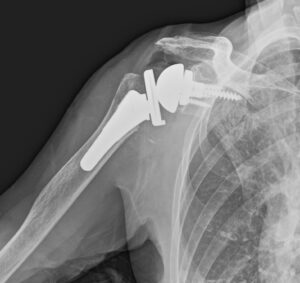

肩関節置換術の経験豊富な、押領司病院(宮崎県小林市)理事長 寺谷威先生をお招きして

右人工肩関節置換術を行いました。

REVERSE型という、新しい概念でデザインされた人工肩関節で、

超高齢で肩関節の機能が低下している方にも有効です